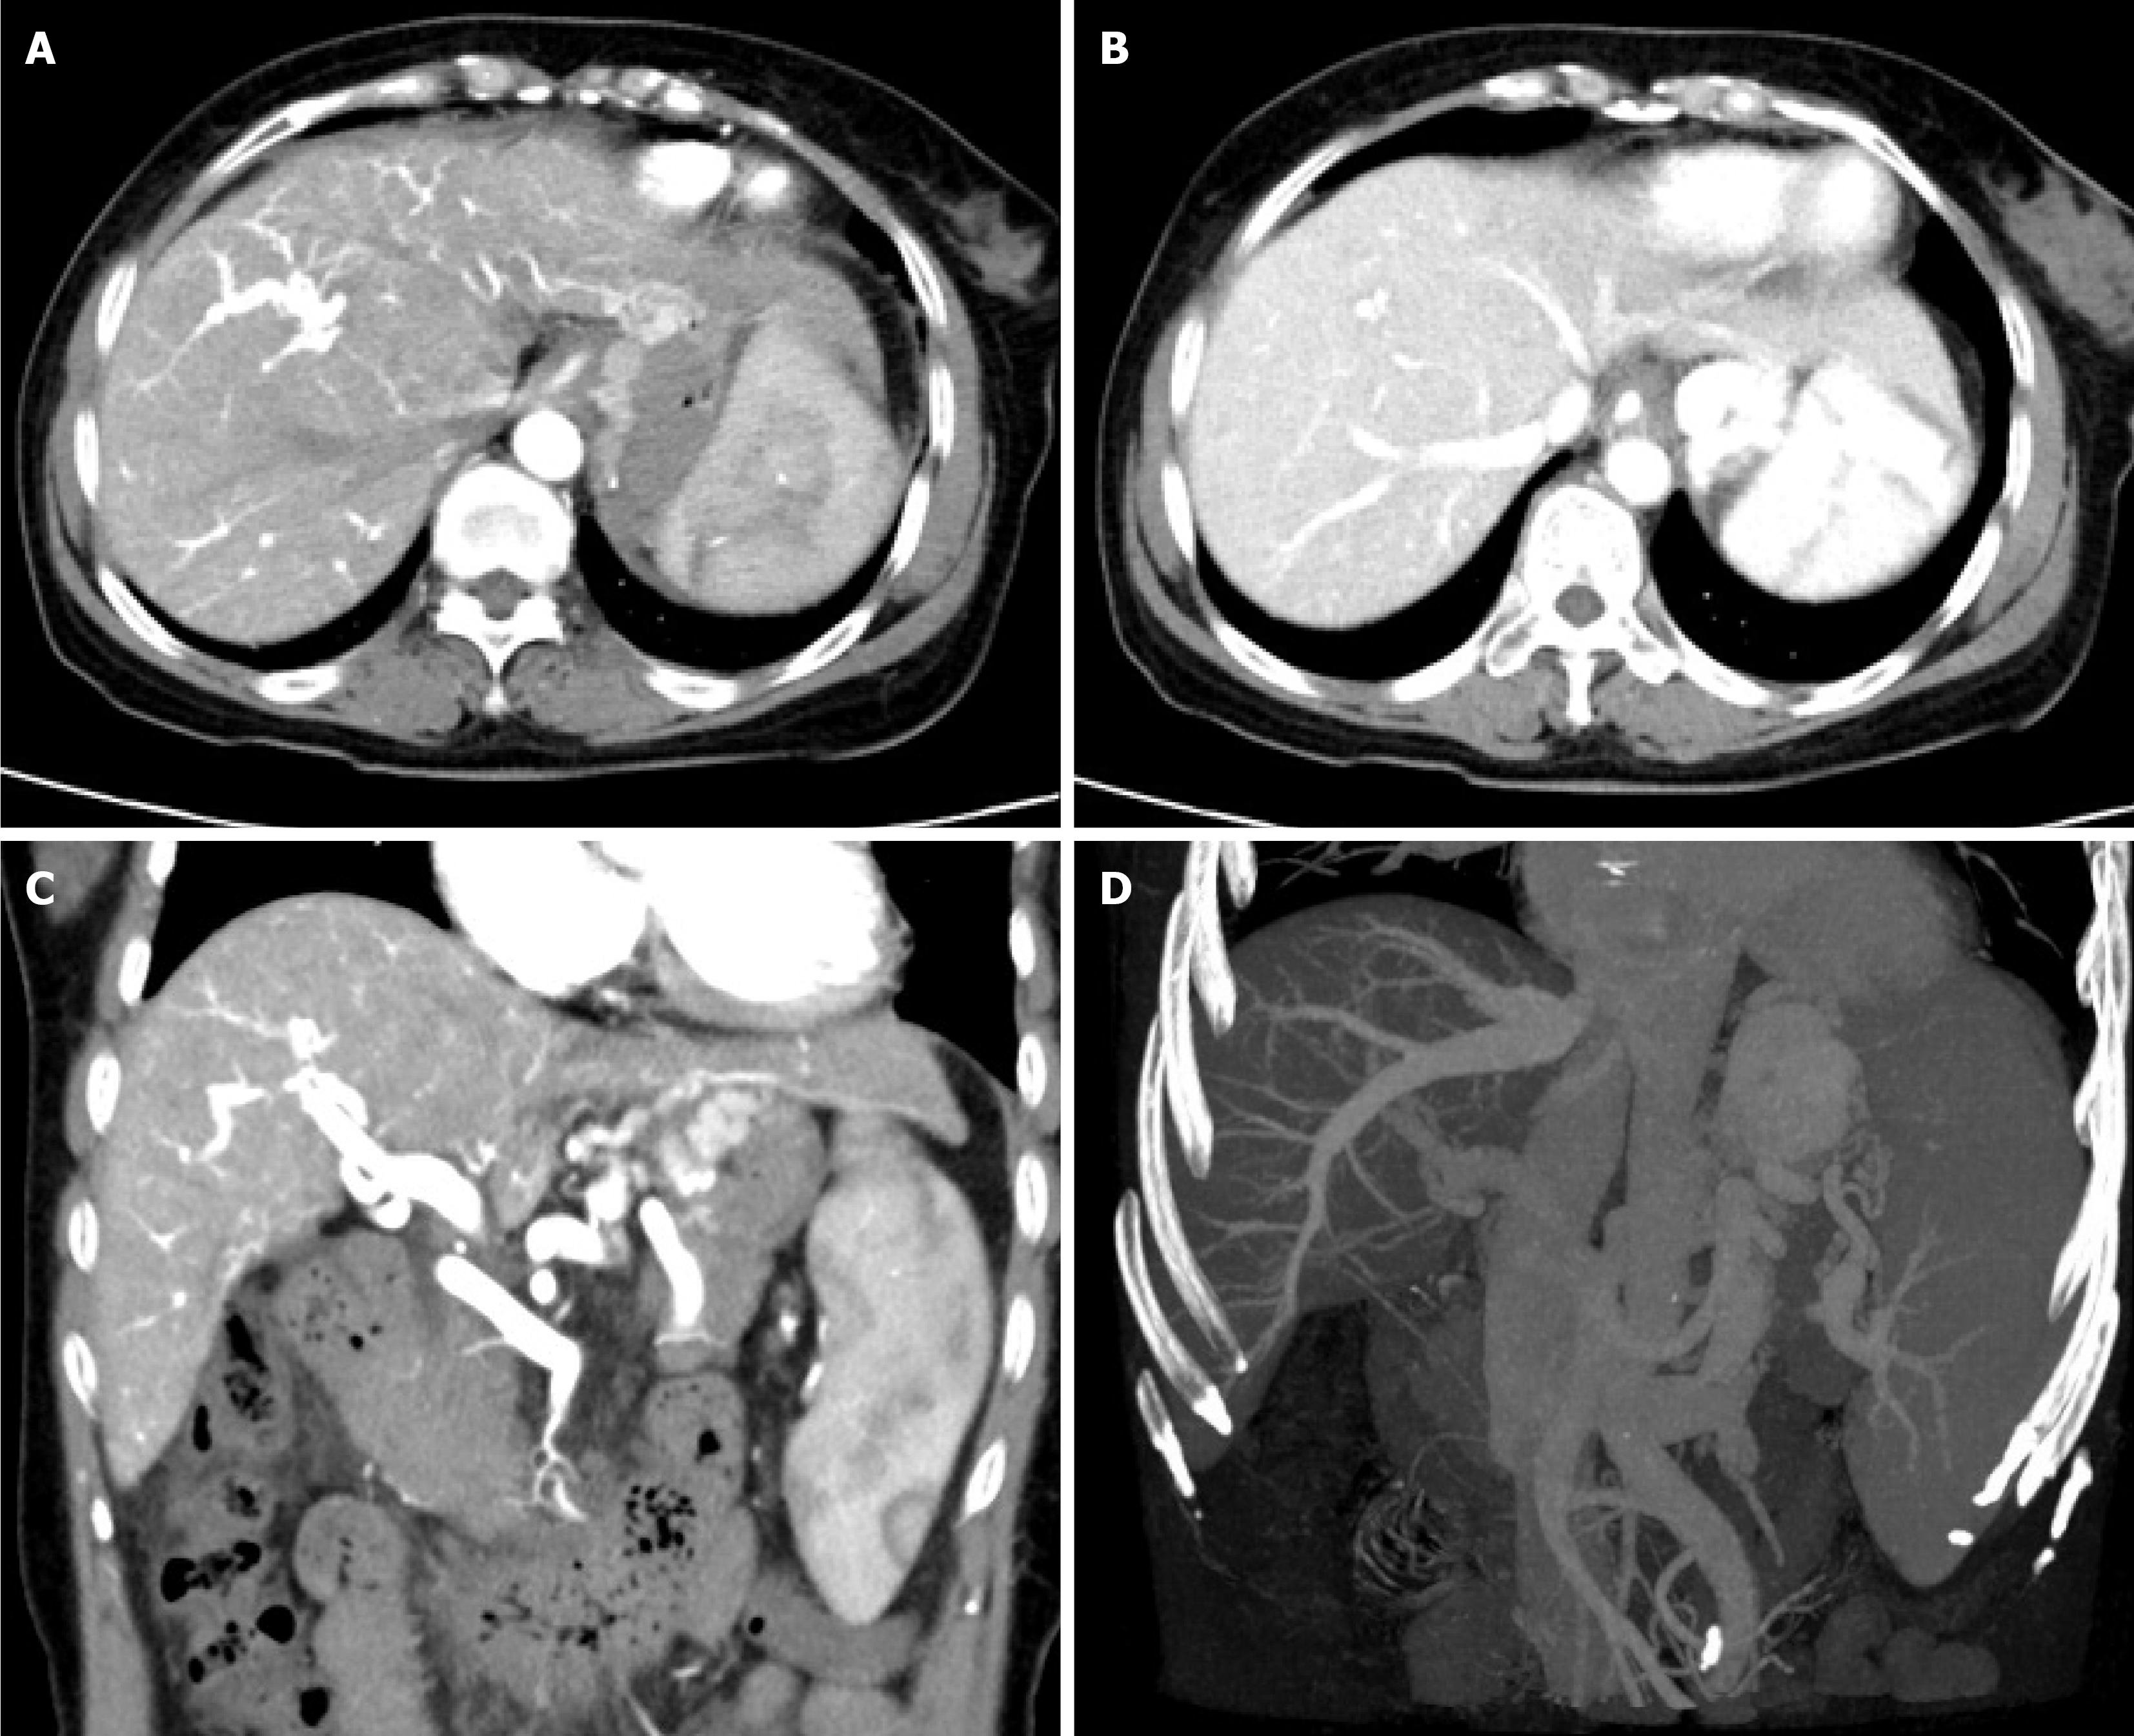

Contrast-enhanced computed tomography (CT) portal angiography revealed: (1) Early enhancement of the main and left/right branches of the portal vein in hepatic arterial-phase, suggesting possible arterioportal fistula; and (2) Liver cirrhosis and splenomegaly with diameter of portal vein being 1.5 cm. Small low-density shadows at the edge of the main portal vein, suspected embolism; left branch portal vein narrowed with spongiform degeneration and multiple collateral circulation formation (Figure 2).

Based on the above results, the patient was diagnosed with diffuse intrahepatic arterioportal fistula, portal hypertension and cavernous transformation of the portal vein. Further history taking revealed a long-standing but previously un